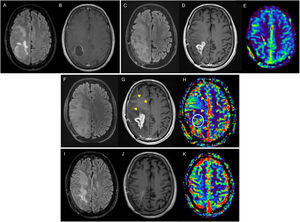

Figure 2.Glioblastoma in a 67-year-old woman in the left temporal-insular region. Follow-up assessment comparing FLAIR and T1-weighted post-contrast sequences from the diagnostic MRI (A, B), 48-h postoperative MRI (C, D) and post-radiotherapy MRI corresponding to the baseline MRI (E, F) to 1στ (G, H), 2νδ (I, J) and 3ρδ (K, L) follow-up MRI scans. Postoperative MRI 48 h later shows complete resection of the tumour-enhancing component (arrowheads). There is a measurable contrast-enhancing lesion in the baseline MRI (arrow) which, in the first repeat scan shows no changes (stable disease), in the second shows a reduction in size (partial response) and by the third, has disappeared (complete response). In subsequent follow-up checks, this last MRI will be the comparison MRI as it is the MRI with the best response.

MRI: magnetic resonance imaging.

The measurement is performed on CE tumour (Fig. 2) and the measurement is re-incorporated in T2/FLAIR images of nCE tumour (Fig. 1). In GB it is recommended to measure only the CE tumour (Fig. 2) and in IDHm and other non-GB gliomas without CE tumour, to measure the nCE tumour (Fig. 1). In cases of GB without CE tumour (molecular GB), nCE tumour assessment is possible, until the appearance of measurable CE tumour. In the case of IDHm and other non-GB gliomas with a mixture of CE and nCE tumour, measurement of both components is possible.